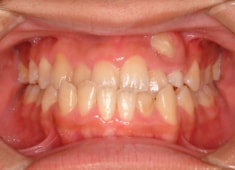

反対咬合+左上3番高位埋伏

(受け口+左上3番目の永久歯が上顎の中に埋まったままはえてきていない)

治療前